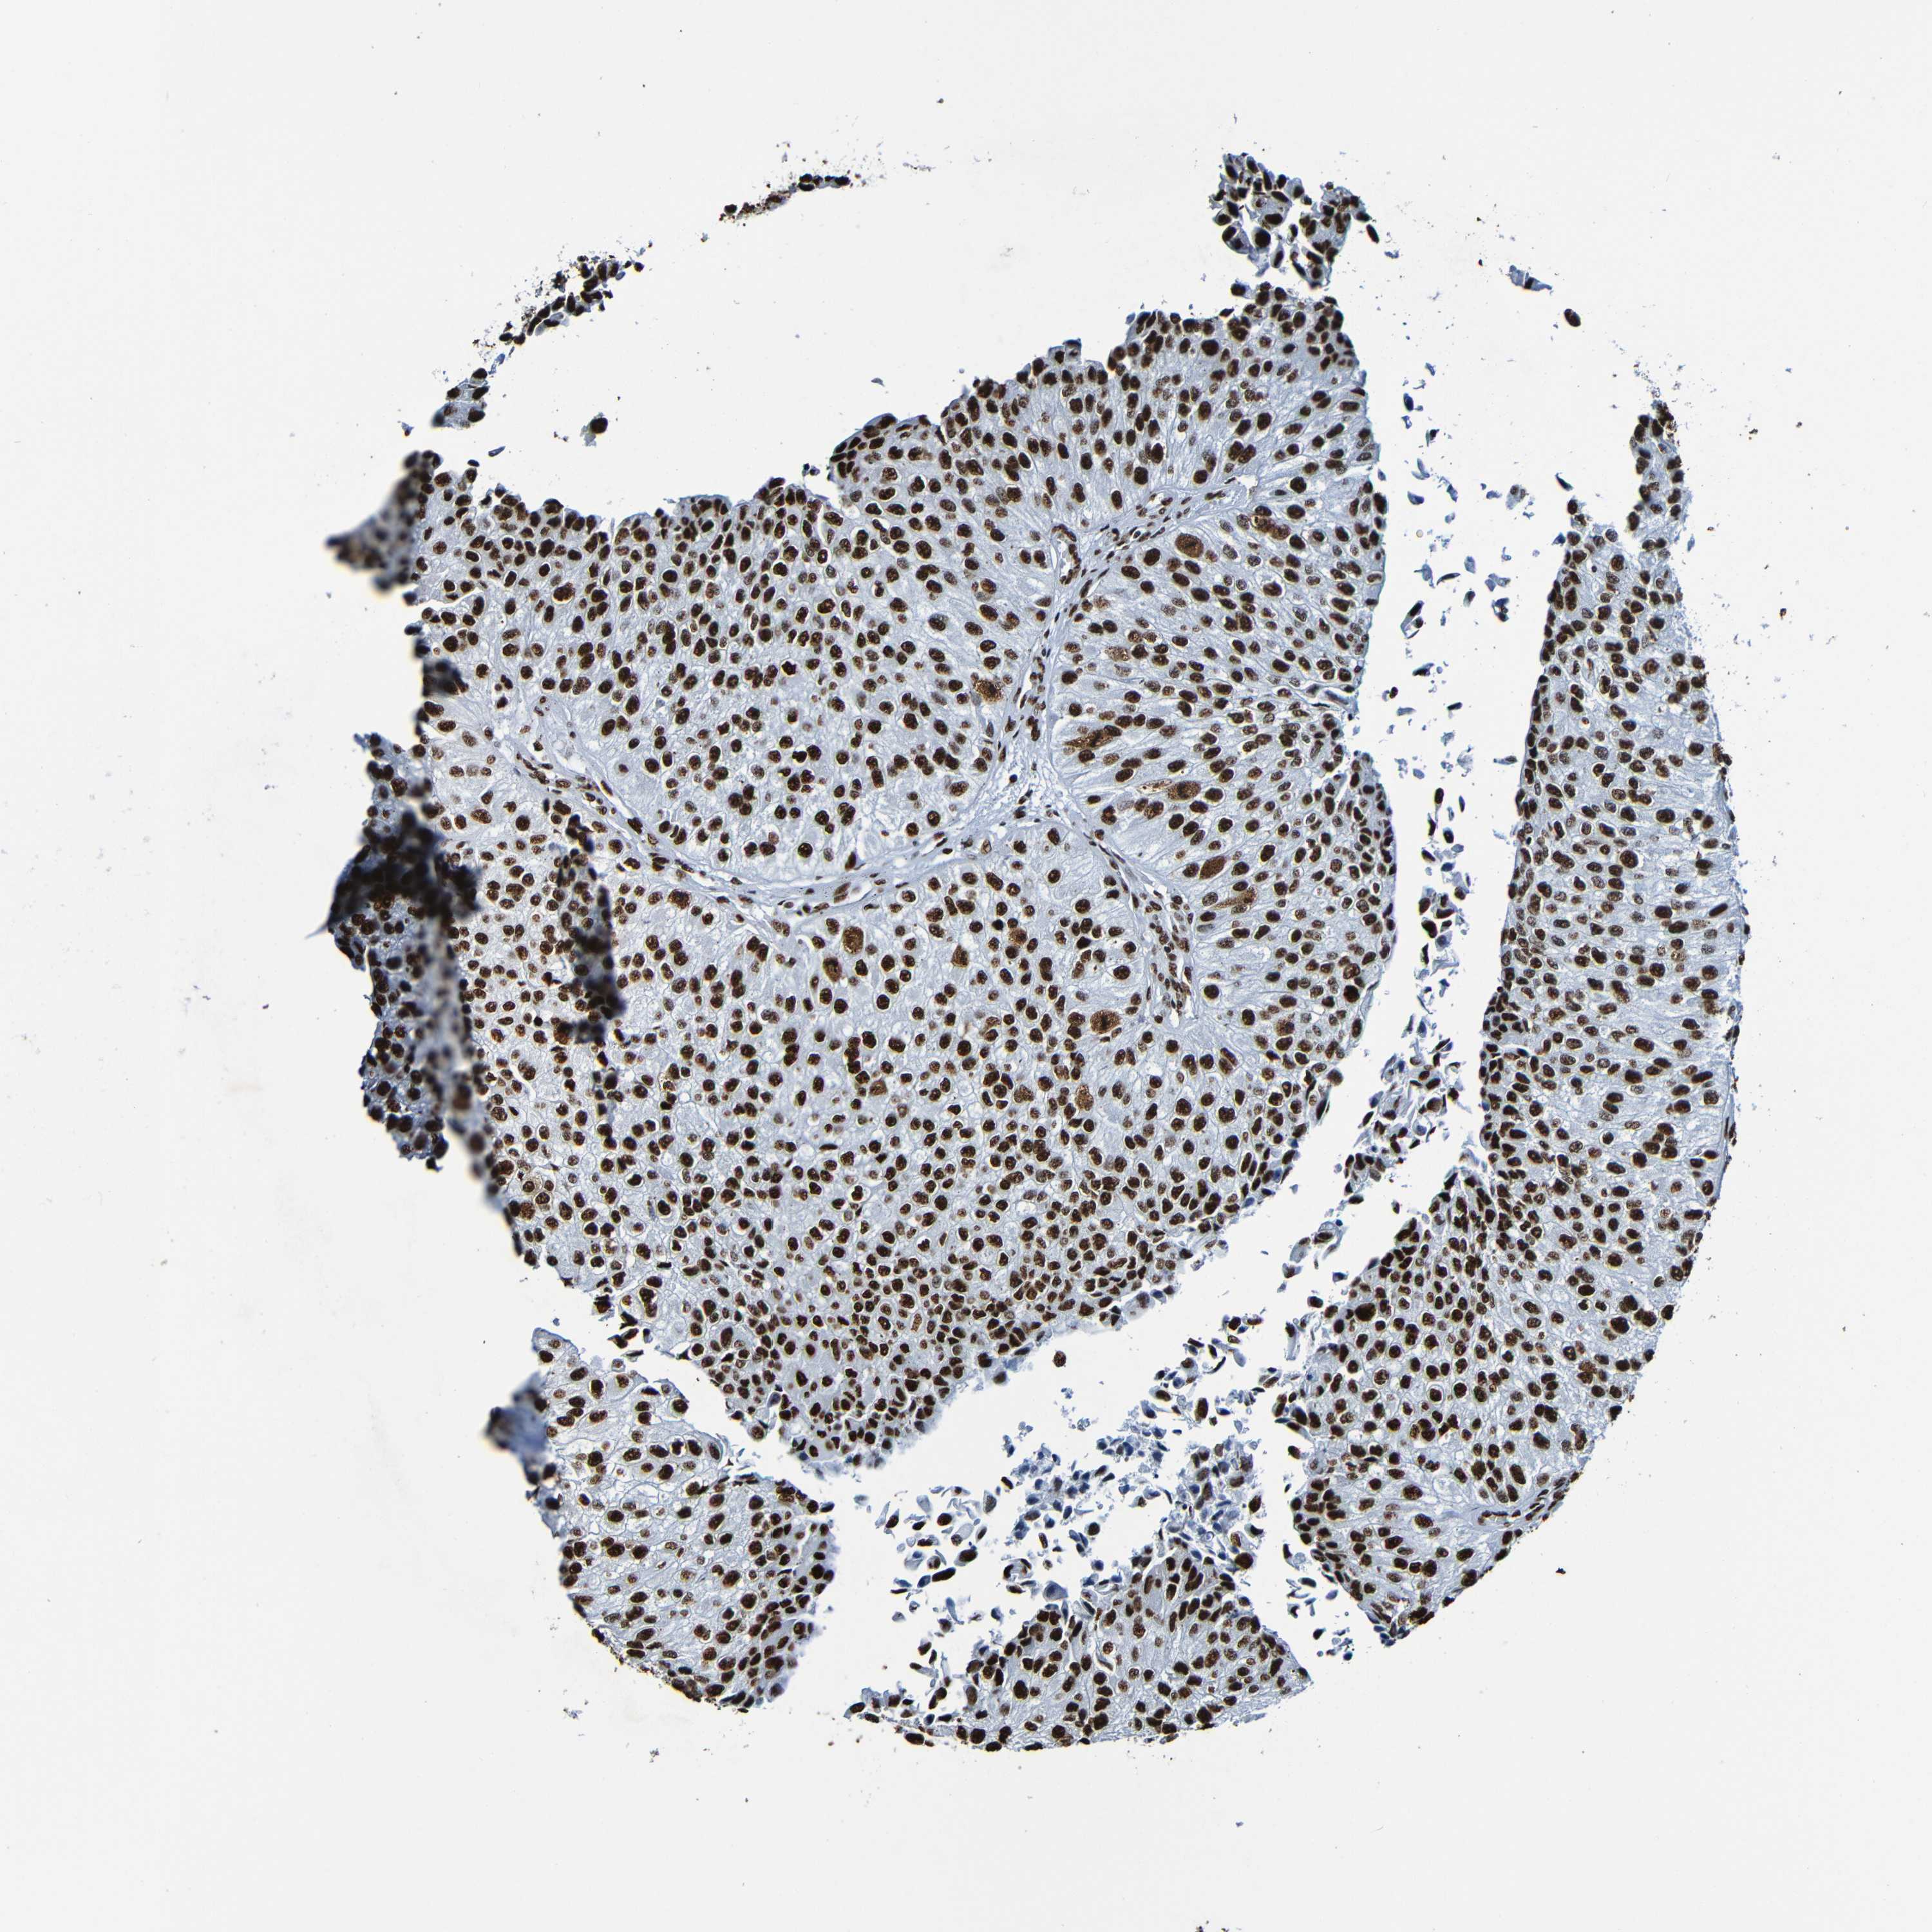

UROTHELIAL CANCER - Protein expressioni

A mouse-over function shows sample information and annotation data. Click on an image to view it in a full screen mode. Samples can be filtered based on level of antibody staining by selecting one or several of the following categories: high, medium, low and not detected. The assay and annotation is described here.

Antibody stainingi

Antibody staining in the annotated cell types in the current human tissue is reported as not detected, low, medium, or high, based on conventional immunohistochemistry profiling in selected tissues. This score is based on the combination of the staining intensity and fraction of stained cells.

Each image is clickable and will lead to virtual microscopy that enables deeper exploration of all samples and also displays staining intensity scores, fraction scores and subcellular localization as well as patient and tissue information for each sample.

Antibody HPA056981

Antibody CAB012986

Staining

High

Medium

Low

Not detected

Intensity

Strong

Moderate

Weak

Negative

Quantity

>75%

75%-25%

<25%

None

Location

Nuclear

Cytoplasmic/membranous

Cytoplasmic/membranous,nuclear

Urothelial carcinoma, High grade